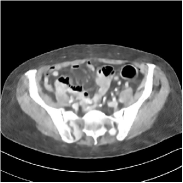

Fig. 2 shows a test example reconstructed using various methods.

Refer to caption

Figure 2: Reconstructions of slice 100 from patient L192 using various methods. The display window is [800 1200] HU.

We observe that PWLS-EP reduces the severe noise and streak artifacts observed in the low-dose FBP images, and the transform learning-based method PWLS-ULTRA further suppresses noise and reconstructs more details of the image such as the zoom-in areas. However, both methods have some blurry artifacts. The standalone FBPConvNet method heavily removes noise and streak artifacts, while introducing several artificial features (e.g., feature indicated by the arrow in the top-right box in Fig. 2). WavResNet denoises the image without introducing artifical features, but still retains some streaks around image boundaries and blurs some details (e.g., feature indicated by the arrow in the bottom-left box in Fig. 2). The state-of-the-art MAP-NN method performs slightly better than WavResNet in terms of suppressing streak artifacts, while it still loses some details as indicated in the zoomed regions. The competing plug-and-play unrolled method—ADMM-Net with WavResNet denoiser—outperforms the standalone WavResNet method, but still has some streak artifacts and blurred details. Compared to these methods, the proposed SUPER methods (SUPER-WRN-EP, SUPER-WRN-ULTRA, SUPER-FCN-EP, and SUPER-FCN-ULTRA) improve the reconstruction quality in terms of removing noise and artifacts, and recovering details more precisely. Two other example comparisons are included in the supplement (Fig. 10 and Fig. 11).